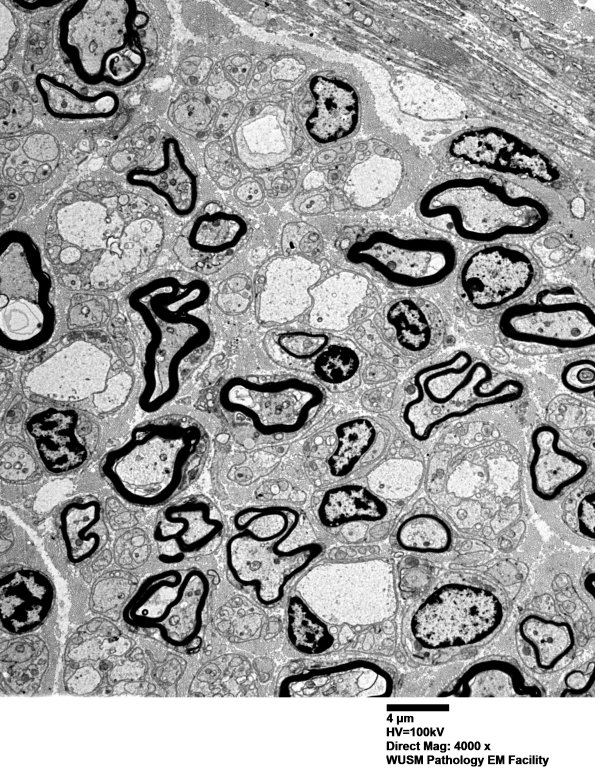

3B1 Low magnification images suggest immature non-myelinated axons, perhaps with a degree of autolytic artifact? (electron micrograph)